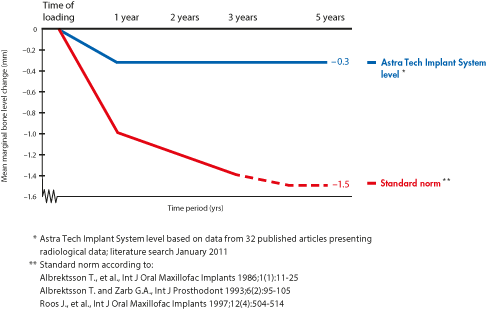

OsseoSpeed – more bone more rapidly

A chemically modified titanium surface with a unique nano scale topography that stimulates early bone healing and speeds up the bone healing process.

MicroThread – biomechanical bone stimulation

Minute threads on implant neck that offer optimal load distribution and stress values.